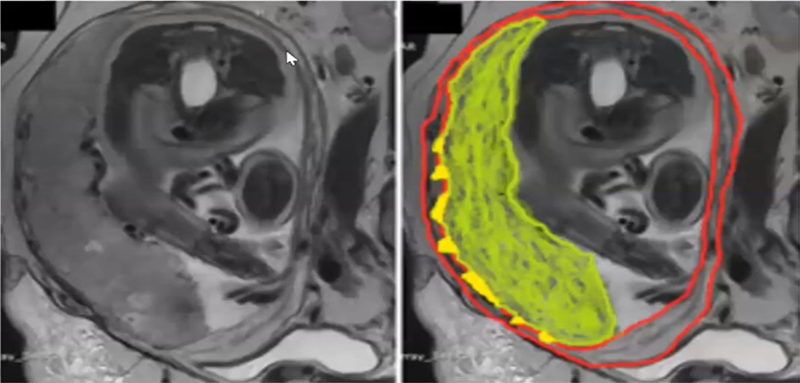

Vai trò của MRI trong chẩn đoán nhau cài răng lược

Đề cập đến vai trò của cộng hưởng từ (MRI) trong chẩn đoán nhau cài răng lược (NCRL), BSCKI. Kiều Trí Lộc cho biết, MRI được chỉ định trong các trường hợp siêu âm chưa đủ cơ sở xác định chẩn đoán, đặc biệt khi bánh nhau bám thành sau, bệnh nhân béo phì hoặc nghi ngờ thể xâm lấn nặng, cần đánh giá chính xác mức độ lan rộng và sự xâm lấn các cơ quan lân cận nhằm lập kế hoạch phẫu thuật phù hợp.

Trên MRI, các dấu hiệu gợi ý NCRL bao gồm: xuất hiện các dải giảm tín hiệu trong bánh nhau trên xung T2, cấu trúc bánh nhau không đồng nhất, tăng sinh và sắp xếp bất thường của hệ mạch trong bánh nhau, các mạch máu xuyên thấu qua cơ tử cung, mất liên tục khu trú lớp cơ tử cung và dấu hiệu xâm lấn trực tiếp của bánh nhau. Trong các trường hợp nặng, có thể ghi nhận dấu hiệu “lều bàng quang”.

Đặc điểm hình ảnh MRI khác nhau theo mức độ xâm lấn:

- Accreta: tử cung to, cấu trúc không đồng nhất, xuất hiện các dải hoặc nốt giảm tín hiệu trên T2, mất ranh giới giữa bánh nhau và cơ tử cung.

- Increta: các dải tín hiệu thấp rõ hơn, mất ranh giới nhau – cơ tử cung, bánh nhau xâm lấn vào lớp cơ, có thể kèm dấu hiệu lồi thanh mạc.

- Percreta: ngoài các dấu hiệu của Increta, bánh nhau xâm lấn xuyên qua thanh mạc tử cung và lan sang các cơ quan lân cận như bàng quang, trực tràng hoặc thành bụng.

.png)

Hình ảnh MRI nhau cài răng lược thể Increta